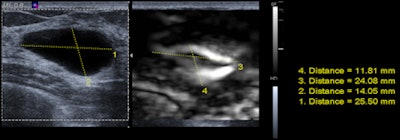

| 46-year-old patient presents for evaluation of left breast nodule after being recalled from screening mammography. Above, mammogram: Nodule present within the left central aspect. Below, B-mode and elastography: Ultrasound shows a cyst present corresponding to area noted on mammogram. Elastography image demonstrates the "bull's-eye" appearance of cysts on elastography. A cyst aspiration was performed and the cyst resolved. Images courtesy of Dr. Stamatia Destounis. |